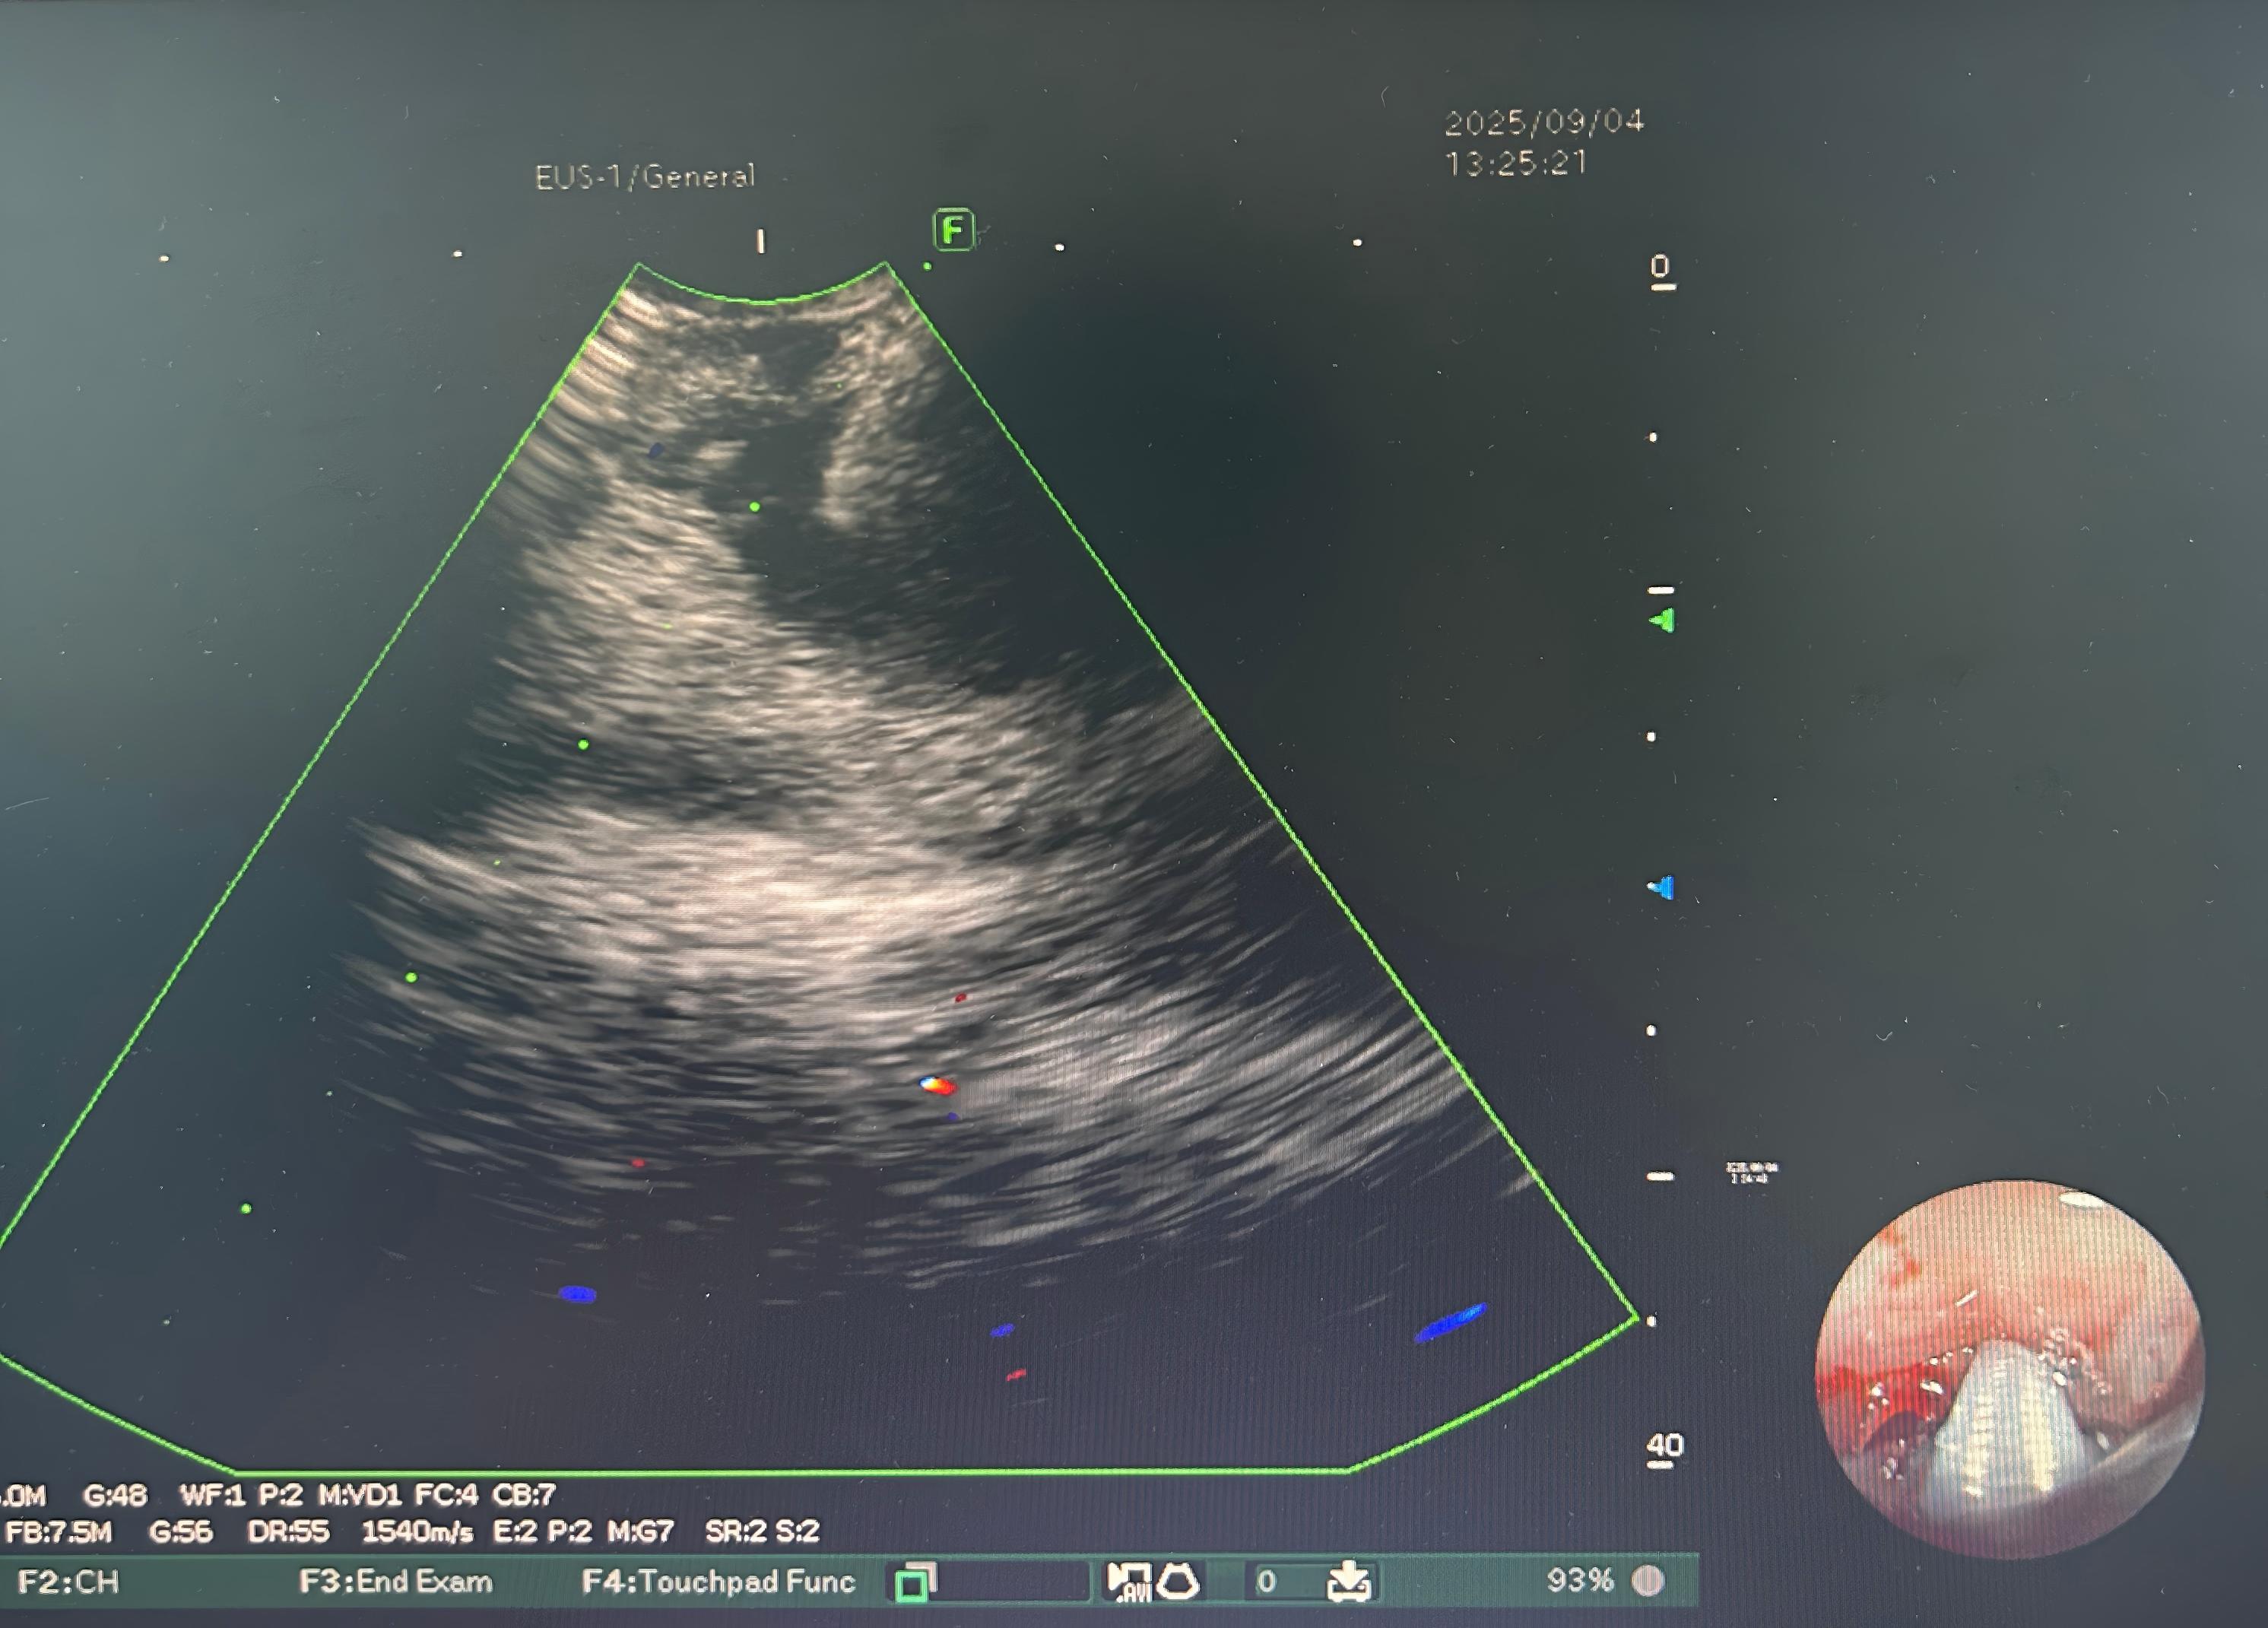

9月4日,在中南大学湘雅三医院呼吸与危重症医学科结对帮扶专家张强的指导下,湘西州人民医院呼吸内镜中心成功开展该院首例超声支气管镜引导下经支气管针吸活检术(EBUS-TBNA),并顺利完成组织病理检查。

患者为72岁男性,因“胸闷、气促1周,活动后加重伴咳嗽咳痰”入院。胸部CT检查显示其纵隔多发淋巴结肿大,性质待定。经湘西州人民医院呼吸治疗中心多学科讨论,团队高度怀疑纵隔肿大淋巴结为恶性转移,需尽快完成病理检查以明确病变性质及来源。

今年9月,湘西州人民医院新引进了超声支气管镜设备,为开展此项技术提供了硬件基础,帮扶专家张强在呼吸内镜诊疗方面经验丰富,在与该院呼吸内镜中心主任文启孝和麻醉科医师米晓燕充分沟通后,他全程指导并示范,协助该院团队成功完成首例全麻喉罩辅助下的EBUS-TBNA术。手术过程顺利,取材充分,术后三天病理结果确诊为前列腺癌纵隔转移,为患者后续针对性治疗争取了宝贵时间。

张强介绍,EBUS-TBNA是一项成熟、安全、精准的微创呼吸内镜技术,目前已广泛应用于肺门、纵隔及肺部病变的诊断,也是肺癌分期的重要工具。该技术具有四大优势:一是微创,穿刺针直径仅约0.8mm,创伤小,术中出血量通常仅为1–10ml;二是安全,实时超声引导可精准定位病灶,有效避开血管及心脏,操作风险低;三是高效,超声实时监控确保穿刺准确,对1cm以上病灶取材成功率高,肺癌诊断率达90%以上;四是舒适,可根据患者情况选择局部麻醉、镇静或全身麻醉,适应范围广,患者体验更优。